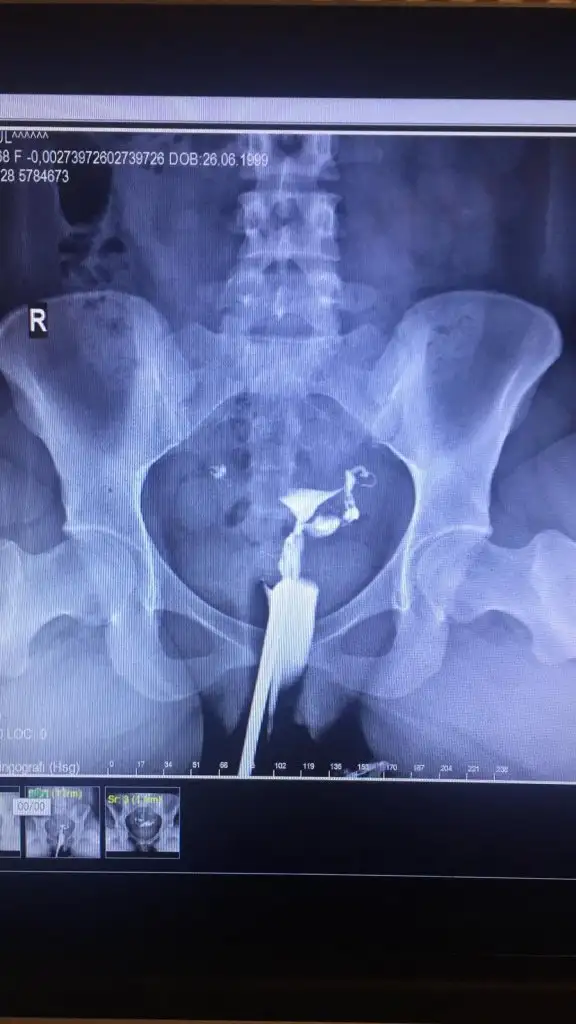

Benim tüplerden sağda zor geçmiş gidince bi soracağım kafama takıldı çünkü fotoda kapalı gibi atsam anlar mısınız tüplerde sıvı olunca nasıl görünüyorYaş 31 benim , hikayemiz kısa zamanda gelişti temmuzdan beri çocuk düşünüyoruz ama 3 ay denemeye olmayinca doktora gittik esimde bir şey çıkmadı benmde hormon testlerim normaldi iki catlatma ignesi denedik olmayinca hsg çekildi sıvı dolu tüp ve kapalı tüptü elde kalanneticesinde gecen hafta tuplerimi alddirdim ve tüp bebege basliyoruz

Sanki solda geçiş yok gibi canım benim de misal sola az ve yavaş giriş var.Bakar mısınız

Yorumlamaya calisirim benim sıvı dolu olan tarafi hatirladigim kadariylaBenim tüplerden sağda zor geçmiş gidince bi soracağım kafama takıldı çünkü fotoda kapalı gibi atsam anlar mısınız tüplerde sıvı olunca nasıl görünüyor